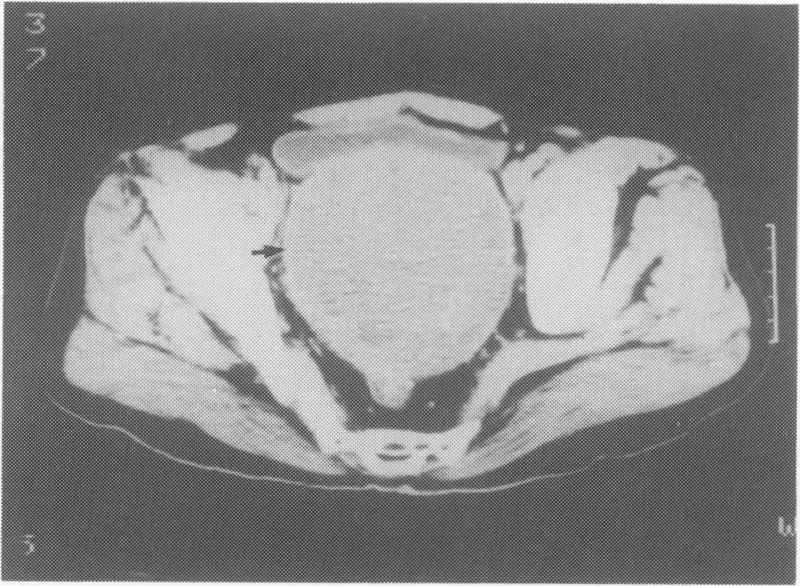

Primary pelvic hydatid cyst is a rare entity. Pelvic hydatid cysts usually present with pressure symptoms involving adjacent organs (bladder and rectum usually). A case of primary pelvic hydatid cyst presenting with obstructive uropathy leading to chronic renal failure is presented. A combination of preoperative albendazole therapy of 1.2 g/day for 8-12 weeks and surgical excision were effective in alleviating the symptoms and improving the renal function.